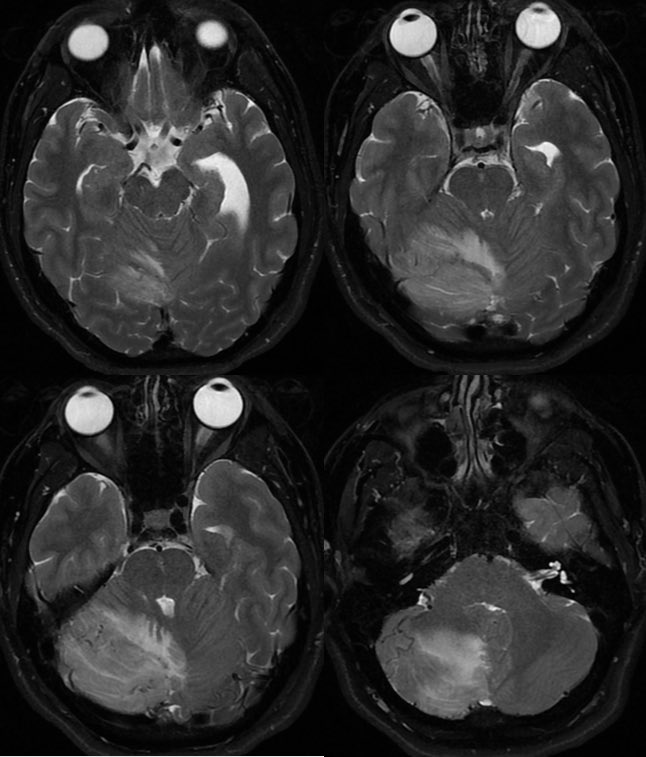

MRI: Enlarged or swollen right cerebellar hemisphere

T2: multiple tortuous flow voids and extensive edema but PRESERVED FOLIA

💡 IF THE FOLIA ARE PRESERVED, THINK ISCHEMIA (NOT TUMOR)

Infiltrating tumor would expand and distort the folia

Enhancement in this case was due to subacute infarct and inflammation